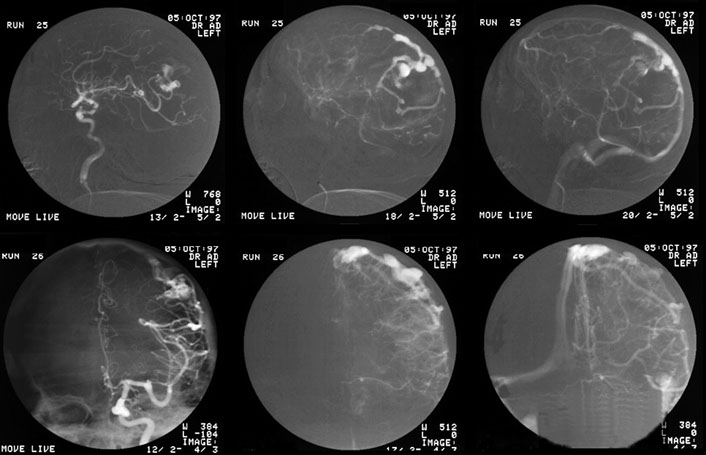

This patient was disturbed in his sleep by a noise in the head. Injection of the left common carotid artery revealed abnormal circulation over the posterior aspect of the brain which was shown to be supplied by a branch of the occipital artery which drained via small vessels into a larger vein.

The flow was gradually occluded by embolisation with particulate material until flow ceased. It is recommended that the venous end is also occluded to prevent recurrence of flow through the fistula via collaterals. This was not done at the initial session and the patient did return with recurrent symptoms two years later.